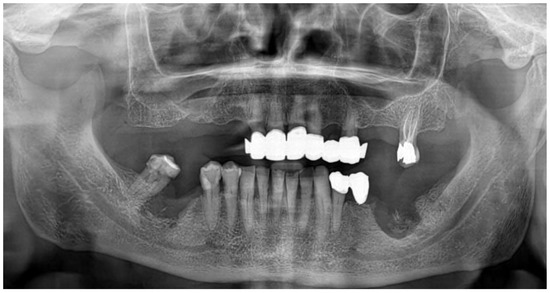

2.1. Case Presentation

- Pre-operative evaluation. The patient undergoes a cone-beam CT exam with a reference plate containing the fiducial markers, fixed on his inferior teeth. The Digital Imaging and Communications in Medicine (DICOM) were imported into the navigation software.

- Surgery timing. The surgeon can follow in real time the ultrasonic tip position onto the system screen displaying the CBCT images and safely identify and remove the necrotic bone surrounding the inferior alveolar nerve on the right side.